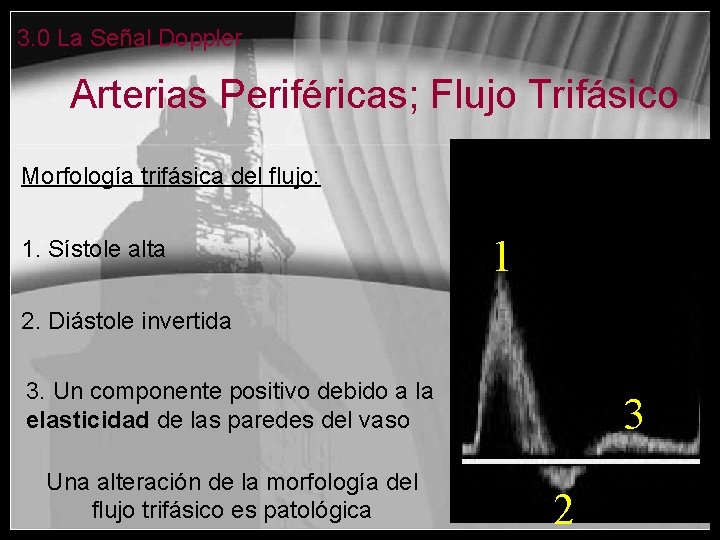

3. 0 La Señal Doppler Arterias Periféricas; Flujo Trifásico Morfología trifásica del flujo: 1. Sístole alta 1 2. Diástole invertida 3. Un componente positivo debido a la elasticidad de las paredes del vaso Una alteración de la morfología del flujo trifásico es patológica 3 2